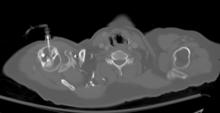

Axial CT with left humeral head EZ IO infusion of contrast.